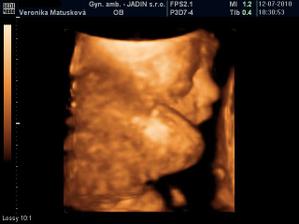

Adamko - 3D/4D

No tot vidno, že je náš syn, sa hanbil a hanbil až sa ukazovať nechcel....ale niekedy sa to podarilo, aj ked to nie je nejaká sláva. Pán doktor nám potvrdil chlapčeka, tak sme radi, vajká ukazoval ako len vedel len toho pipíka stále schovával. Ale je to za nami, pán doktor nás pekne popísal čo je kde, poodmeral nás a povedal, že je všetko v poriadku.